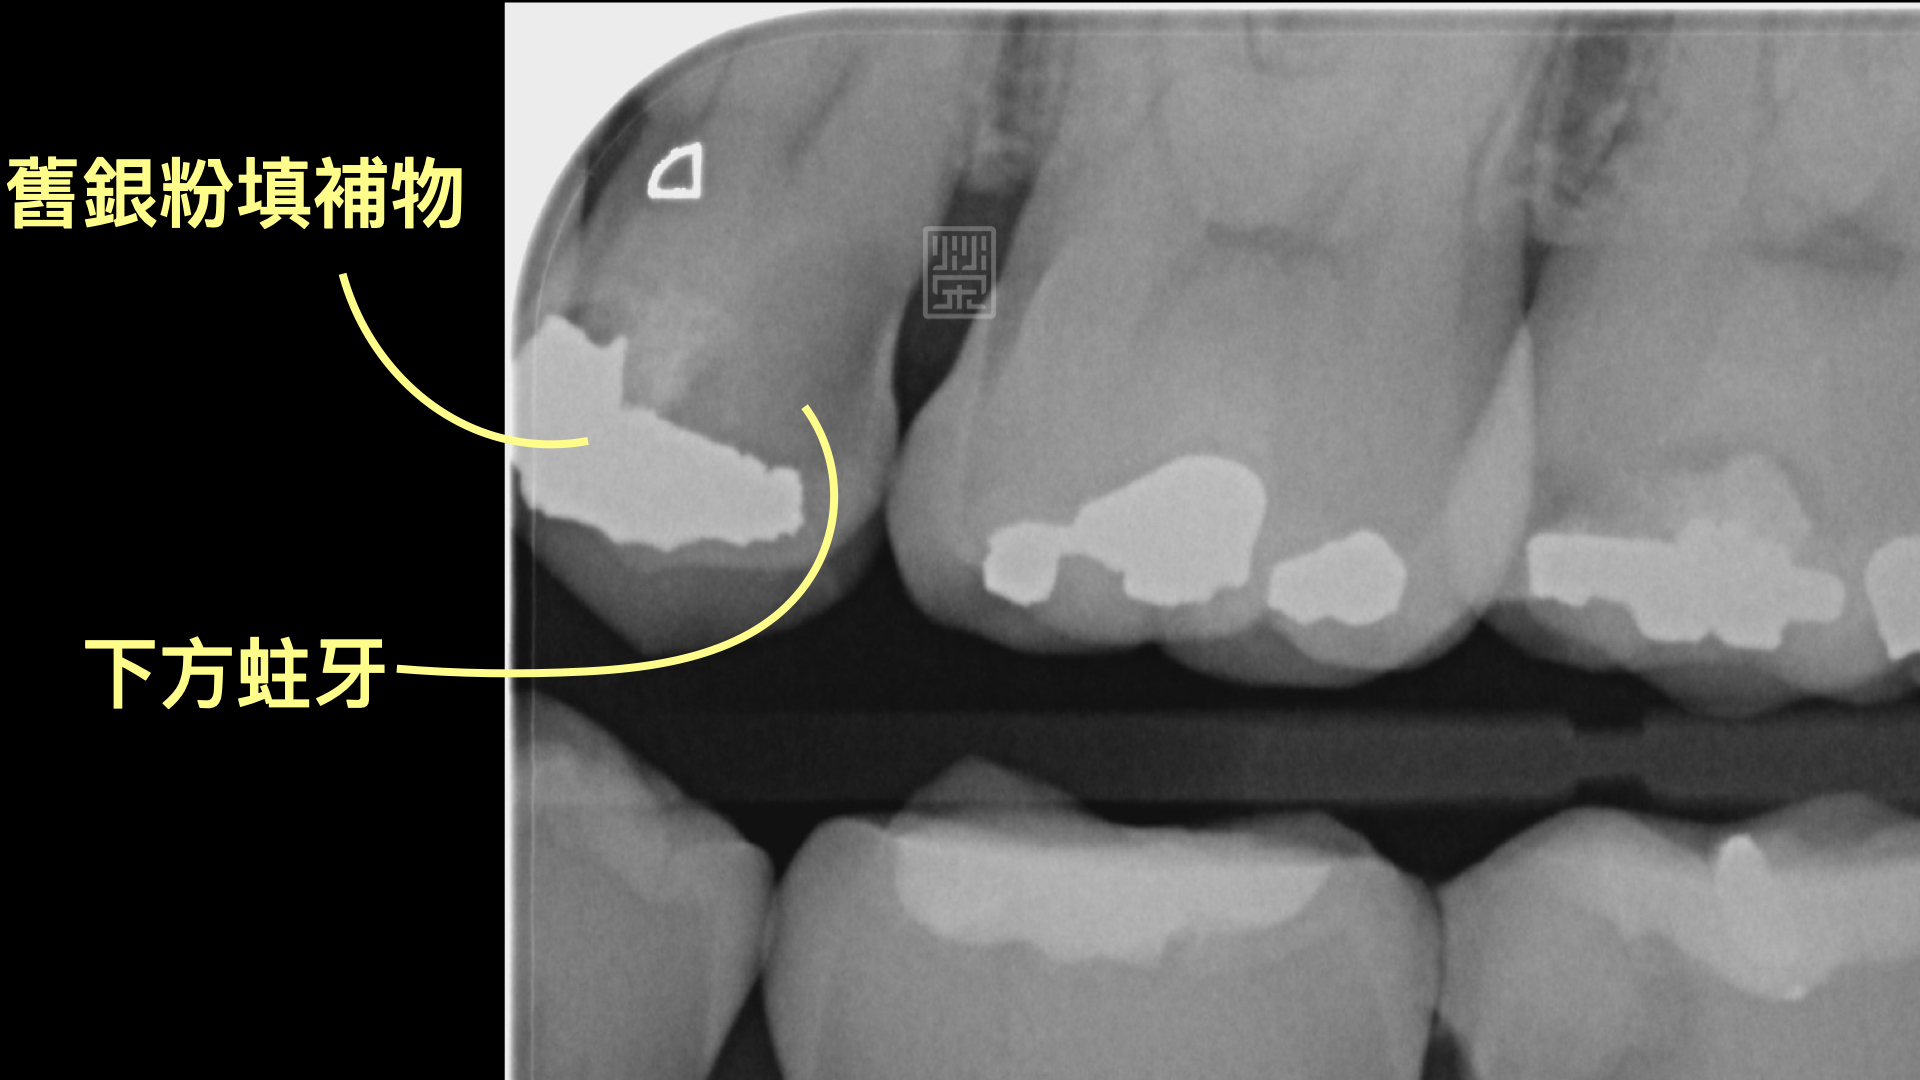

X光檢查下,雖然咬合面的蛀洞小,但是下方有很嚴重的蛀牙

小臼齒齒縫間有個小洞,很容易塞食物